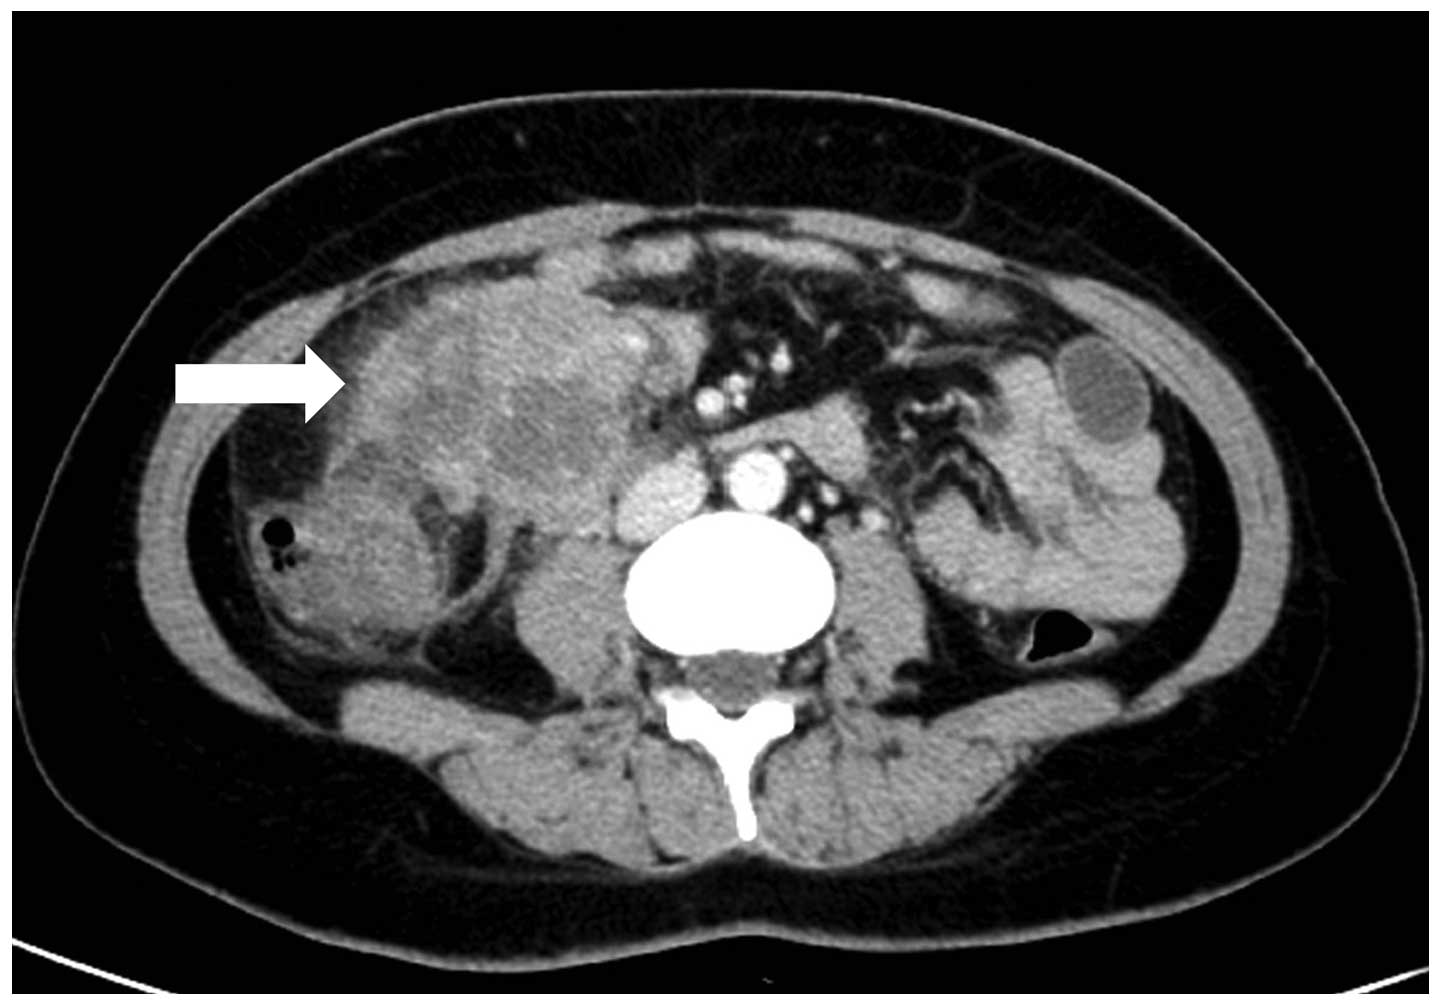

Imaging

A normal chest X-ray was obtained. An abdominopelvic contrast-enhanced computed tomography (CT) scan (Fig. 1) revealed: i) A bulky soft-tissue dense mass in the middle of the ascending colon and superior to the ileocecum; heterogeneous enhancement following enhanced scan; thickened anterior of the renal fascia of the right kidney and local parietal peritoneum. ii) Multiple renal cysts in both kidneys. The CT scan did not indicate any bowel involvement, distant metastasis or abdominal lymph node enlargement. The abdominal ultrasound did not reveal any coexisting lesion in the hepato-pancreato-biliary system. Single-photon emission computed tomography (SPECT) renal imaging (99mTc-DTPA) revealed that the glomerular filtration rate was slightly decreased and the upper urinary tract had unobstructed drainage in the two kidneys.

Figure 1.

Abdominopelvic contrast-enhanced computed tomography scan revealed a bulky soft-tissue dense mass (white arrow) in the middle of the ascending colon and superior to the ileocecum. Heterogeneous enhancement was noted following the enhanced scan.